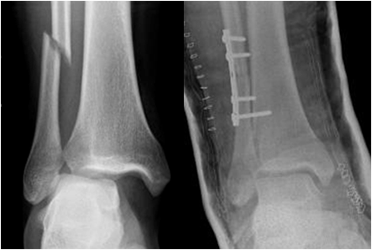

A: Rx AP. Fractura no desplazada del peroné distal. Se aprecia incremento del espacio articular tibio peroneo distal y subluxación de la articulación tibioastragalina, por lesión ligamentaria.

B: Rx AP. Cambios PostQx con reducción de la subluxación y estabilización de la fractura en el peroné.